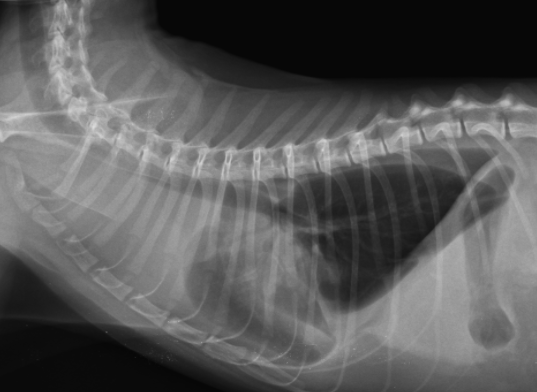

貓 淋巴癌 胸水 胸腔前縱膈腔腫瘤 腹腔淋巴結腫大 化療 不是感冒 首頁 病例分享 腫瘤科 貓 淋巴癌 胸水 胸腔前縱膈腔腫瘤 腹腔淋巴結腫大 化療 不是感冒 1歲已絕育母貓,就診前一周精神食慾下降、咳嗽,在他院診斷感冒治療無效而就醫。 經急診醫師檢查發現有嚴重胸水、前縱膈團塊、腹腔淋巴結腫大。 排除心臟病、白血病等等鑑別診斷後採樣確診為貓咪的淋巴癌。 雖然淋巴癌的治癒率非常低,但對化療有良好反應的機率很高,於是後續開始化療計畫。 影像檢查結果 嚴重胸水 抽完胸水後發現前縱膈腔團塊. 腹腔內淋巴結多發腫大 病理切片: 箭頭所指處為有絲分裂中的淋巴癌細胞